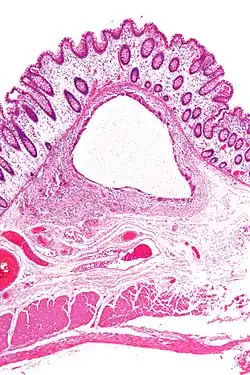

In the lungs, emphysema involves enlargement of the distal airspaces,[2] and is a major feature of chronic obstructive pulmonary disease (COPD). Other pneumatoses in the lungs are focal (localized) blebs and bullae, pulmonary cysts and cavities.

A lung cyst, or pulmonary cyst, encloses a small volume of air, and has a wall thickness of up to 4 mm.[3] A minimum wall thickness of 1 mm has been suggested,[3] but thin-walled pockets may be included in the definition as well.[4] Pulmonary cysts are not associated with either smoking or emphysema.[5]

A lung cavity has a wall thickness of more than 4 mm.[3]